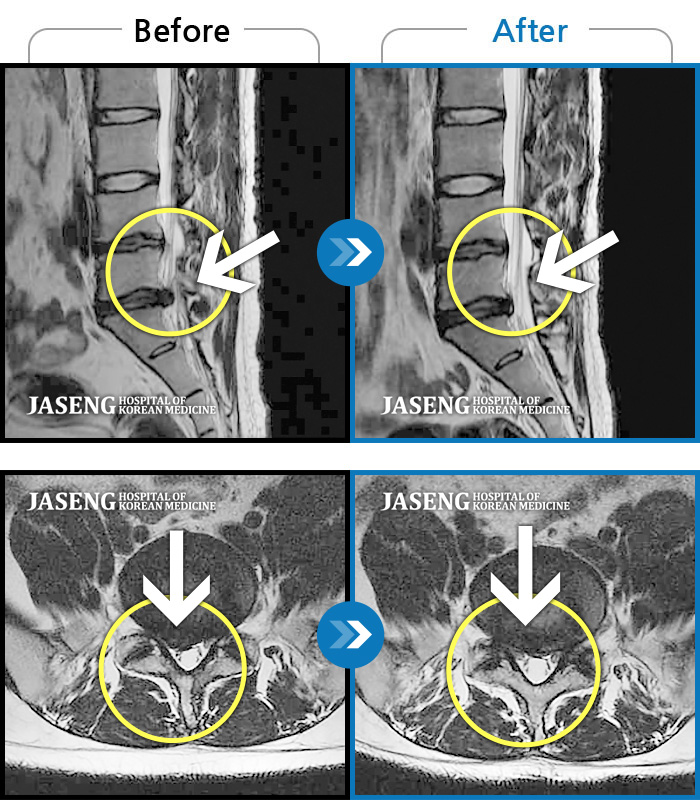

허리디스크

잠실 · 한상욱 원장

허리가 많이 아프고 왼쪽 다리가 저려 움직이기가 힘들다.

촬영시기

2022.01.19 ~ 2022.11.14

2022.12.02